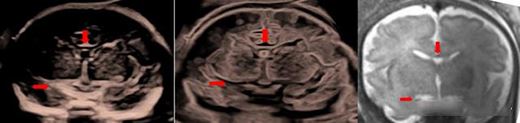

利器2:CrystalVue技術可清晰顯示內部組織結構,如透明隔腔側腦室后角,以及胼胝體,海馬溝等,精準區分組織邊界;

水晶成像顯示透明隔腔側腦室后角

水晶成像顯示胼胝體,海馬溝

此外,在早孕期胎兒中樞神經系統檢查,CrystalVue還能為腦室系統提供全新的三維成像,更早的了解神經發育變化,評估和診斷胎兒中樞神經系統異常;反轉水晶成像更好顯示胎兒大腦溝回。

早孕期 胎兒腦室三維成像